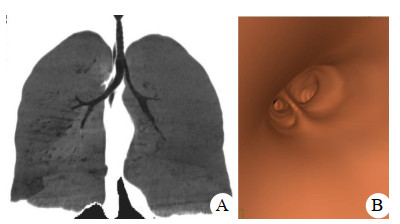

初步诊断后立即持续生命体征监测,开放静脉通路,吸氧,鼻腔填塞止血,完善实验室检查;鼻导管吸氧10 L/min,10 min后血氧饱和度仍维持在80%~85%,即准备行气管插管后再送放射科行颅脑及胸部影像学检查。急诊科医师在视频喉镜辅助下进行气管插管术(气管导管内径7.0 mm),但连续3次在确认气管导管前端进入声门5 cm后再无法置入,改用气管导管旋转或加入管芯等多种手法仍然无法置入,最后请麻醉科医师会诊。麻醉医师携带纤维支气管镜增援,当纤维支气管镜通过气管导管观察发现,远端气道狭窄。更换小号气管导管(内径5.0 mm),通过声门5 cm后仍然无法置入到位。与家属沟通,家属反馈,患者既往无呼吸系统疾病,偶有上呼吸道感染,但病程及预后无异常。患者5年前在上海一所整形医院麻醉时曾出现过这种情况,手术被院方拒绝。请耳鼻喉科、呼吸科医师会诊,建议先行颅脑及胸部影像学检查后再决定气道管理方案。CT三维重塑及虚拟支气管镜成像系统(Osirix MD version 12.0, Pixmeo SARL company)显示(图 1),气管长度仅5 cm,左右支气管内径分别为8 mm、5 mm。考虑患者手术要求及颅脑康复预后的时间,根据耳鼻喉科建议采用了气管切开导管管理气道。出院后一年随访,患者神经功能恢复良好,气管造瘘口自然愈合,发音正常,无呼吸系统并发症。

| 图 1 患者影像学检查结果(A:患者气管支气管CT三维重塑;B:虚拟支气管镜成像) |

本例患者年轻女性,气管支气管发育先天异常。在不清楚患者气管解剖异常下气管插管,由于右侧支气管开口的位置优势,每次气管导管会顺势进入狭窄的右侧支气管并且卡塞,亦使支气管镜观察到的远端气道狭窄位置被误认为在气管。气管导管较长的套囊设计使导管需要置入至声门下6~9 cm,限制了它在气管较短患者中的使用。急诊患者多数缺乏气道影像学资料,当遇到气管导管放置困难情况时,采用纤维支气管镜对气道进行全面检查是非常必要,并且在条件允许情况下可实施纤维支气管镜引导下气管插管术。